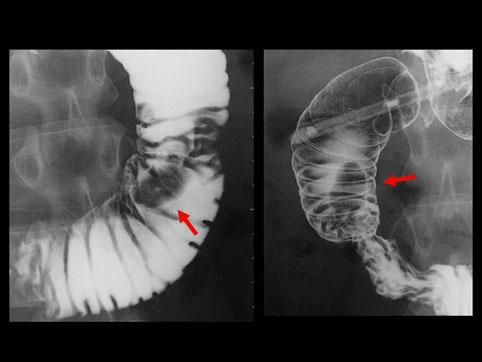

症例提示(所在地,施設名等): 福岡県・ 九州大学病院 (放射線科からの提供症例)

疾患(病理主体)の分類腫瘍様病変/過形成ポリープ

部位(臓器別)十二指腸/下行脚

検査方法X-P

腫瘍の肉眼分類0型(表在型)/I型(Ip)

病変の最大径(ミリ)15〜19